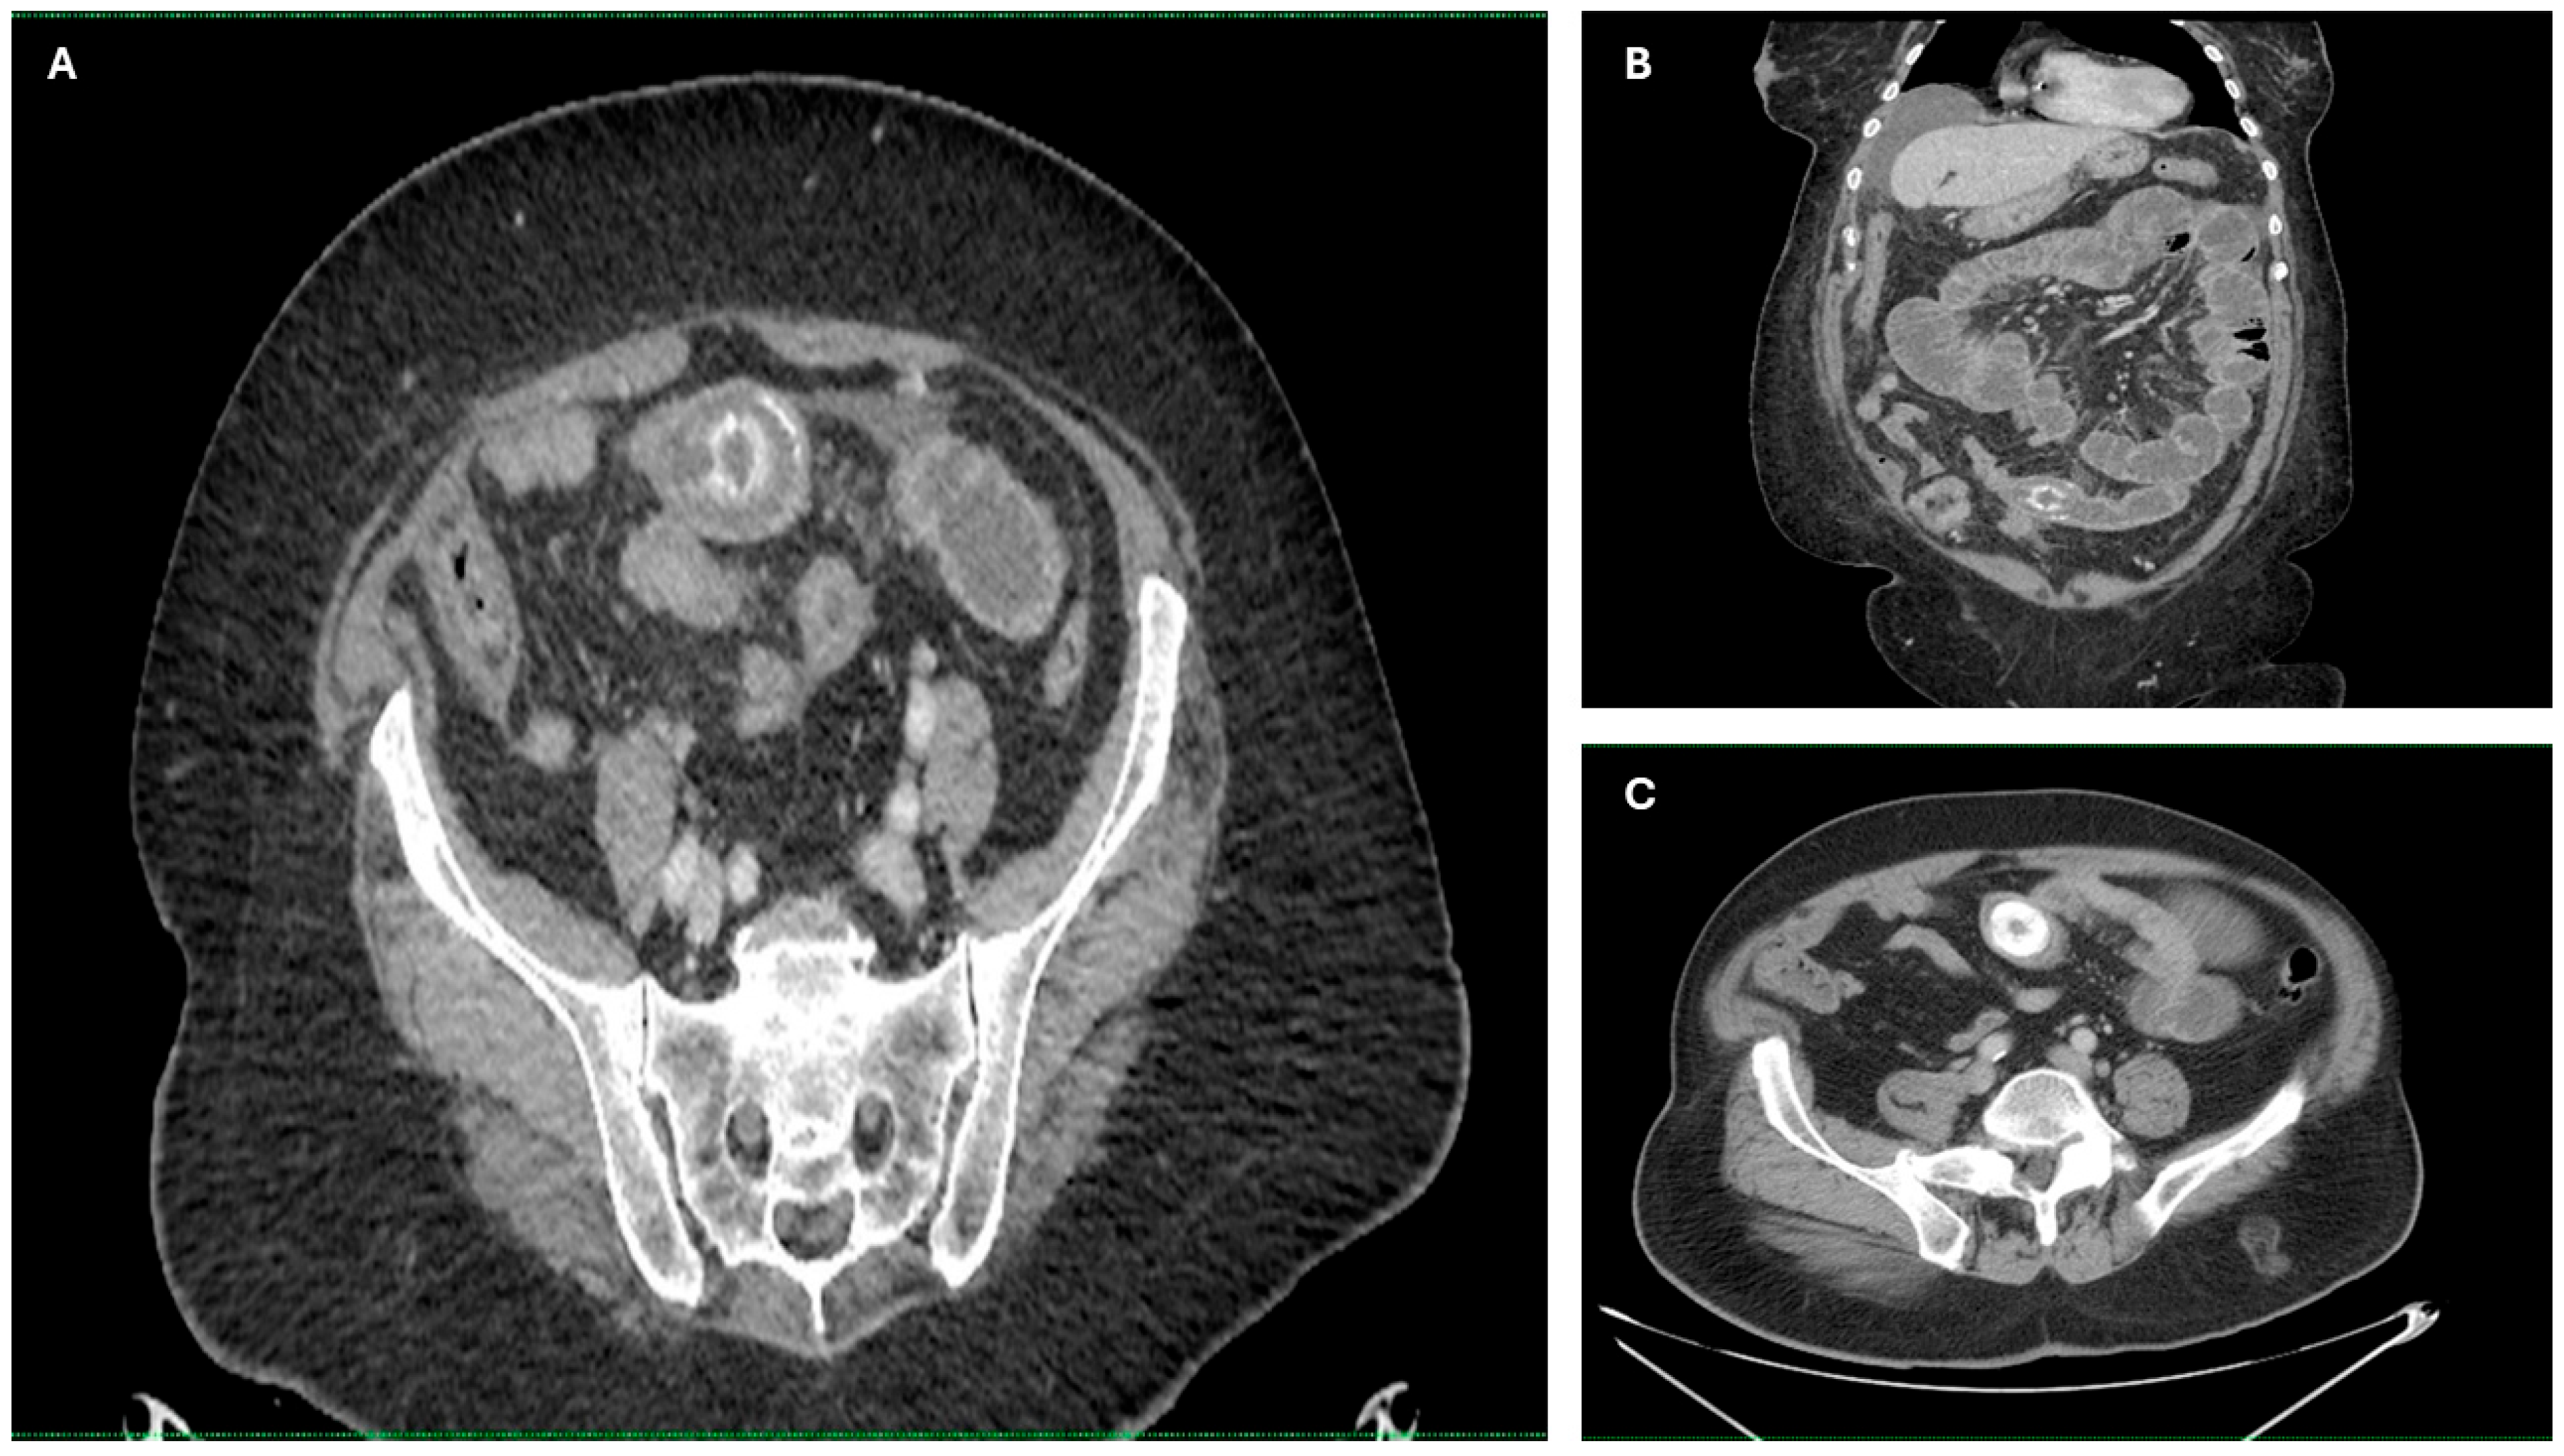

Imaging findings were consistent with biliary ileus, characterized by the presence of ectopic gallstones within the gastrointestinal tract. As shown in Figure 3A–C, axial and coronal CT images demonstrated radiopaque enteric gallstones. Figure 4 highlights a gallstone associated with a cholecystoduodenal fistula. Further axial and coronal sections (Figure 5A–C) show additional enteric gallstones, including one in the rectal ampulla.

Figure 4. Enteric gallstone associated with cholecystoduodenal fistula. Coronal reconstructed CT images showing an ectopic gallstone within the intestine, secondary to a cholecystoduodenal fistula—a classic radiological finding in biliary ileus. (AC) Coronal reconstructions showing multiple distended small bowel loops upstream from the obstruction site, with the intraluminal gallstone visible in the terminal ileum. Acquisition with 5 mm slice thickness and 3 mm reconstruction. Images have been cropped and zoomed for optimal visualization while maintaining the original scale; a 10 mm scale bar is included in each panel.